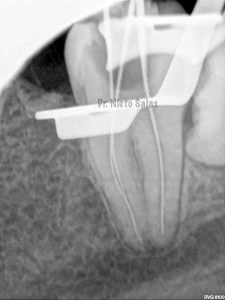

La otra pieza, el 3.7, se instrumentó con sistema Protaper y obturación con Ola continua de Calor y un back-filling con la pistola Obtura II.

(buscamos siempre algún conducto lateral, para intentar asegurarnos de su limpieza)

Y una en las demás proyecciones MESIO Y DISTO: